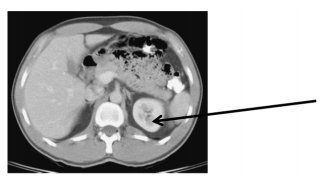

Qual é o ponto assinalado na imagem de tomografia a seguir?

Provas